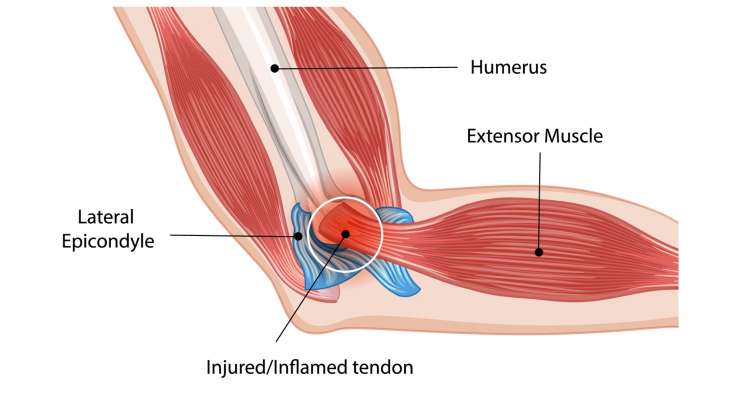

Эпикондилит, локоть гольфиста или теннисиста

Эпикондилит, известный как теннисный или гольф-локоть, профессор, доктор медицины Франк Мартечшлегер сначала лечит консервативно с помощью физиотерапии, ударно-волновой терапии или лечения собственным кровью, а при стойких симптомах — хирургическим путем с помощью реконструкции сухожилий.

Лечение локтей в Мюнхене

В области хирургии локтя профессор Франк Мартешлегер (Frank Martetschläger) в Мюнхене предлагает широкий спектр современных методов диагностики и лечения. К ним относятся артроз локтя, нестабильность локтя, эпикондилит (теннисный и гольф-локоть), переломы локтя, а также хронические воспаления или ограничения подвижности. В зависимости от результатов обследования лечение проводится консервативно — например, с помощью физиотерапии, инъекций или ударно-волновой терапии — или хирургически, в большинстве случаев с помощью минимально инвазивной артроскопической техники. При сложных травмах могут потребоваться открытые вмешательства и реконструктивные операции для восстановления функции и стабильности сустава. Пациенты в Мюнхене получают преимущества точной диагностики, комплексного подхода к лечению и опыта международно признанного специалиста по локтевому суставу.